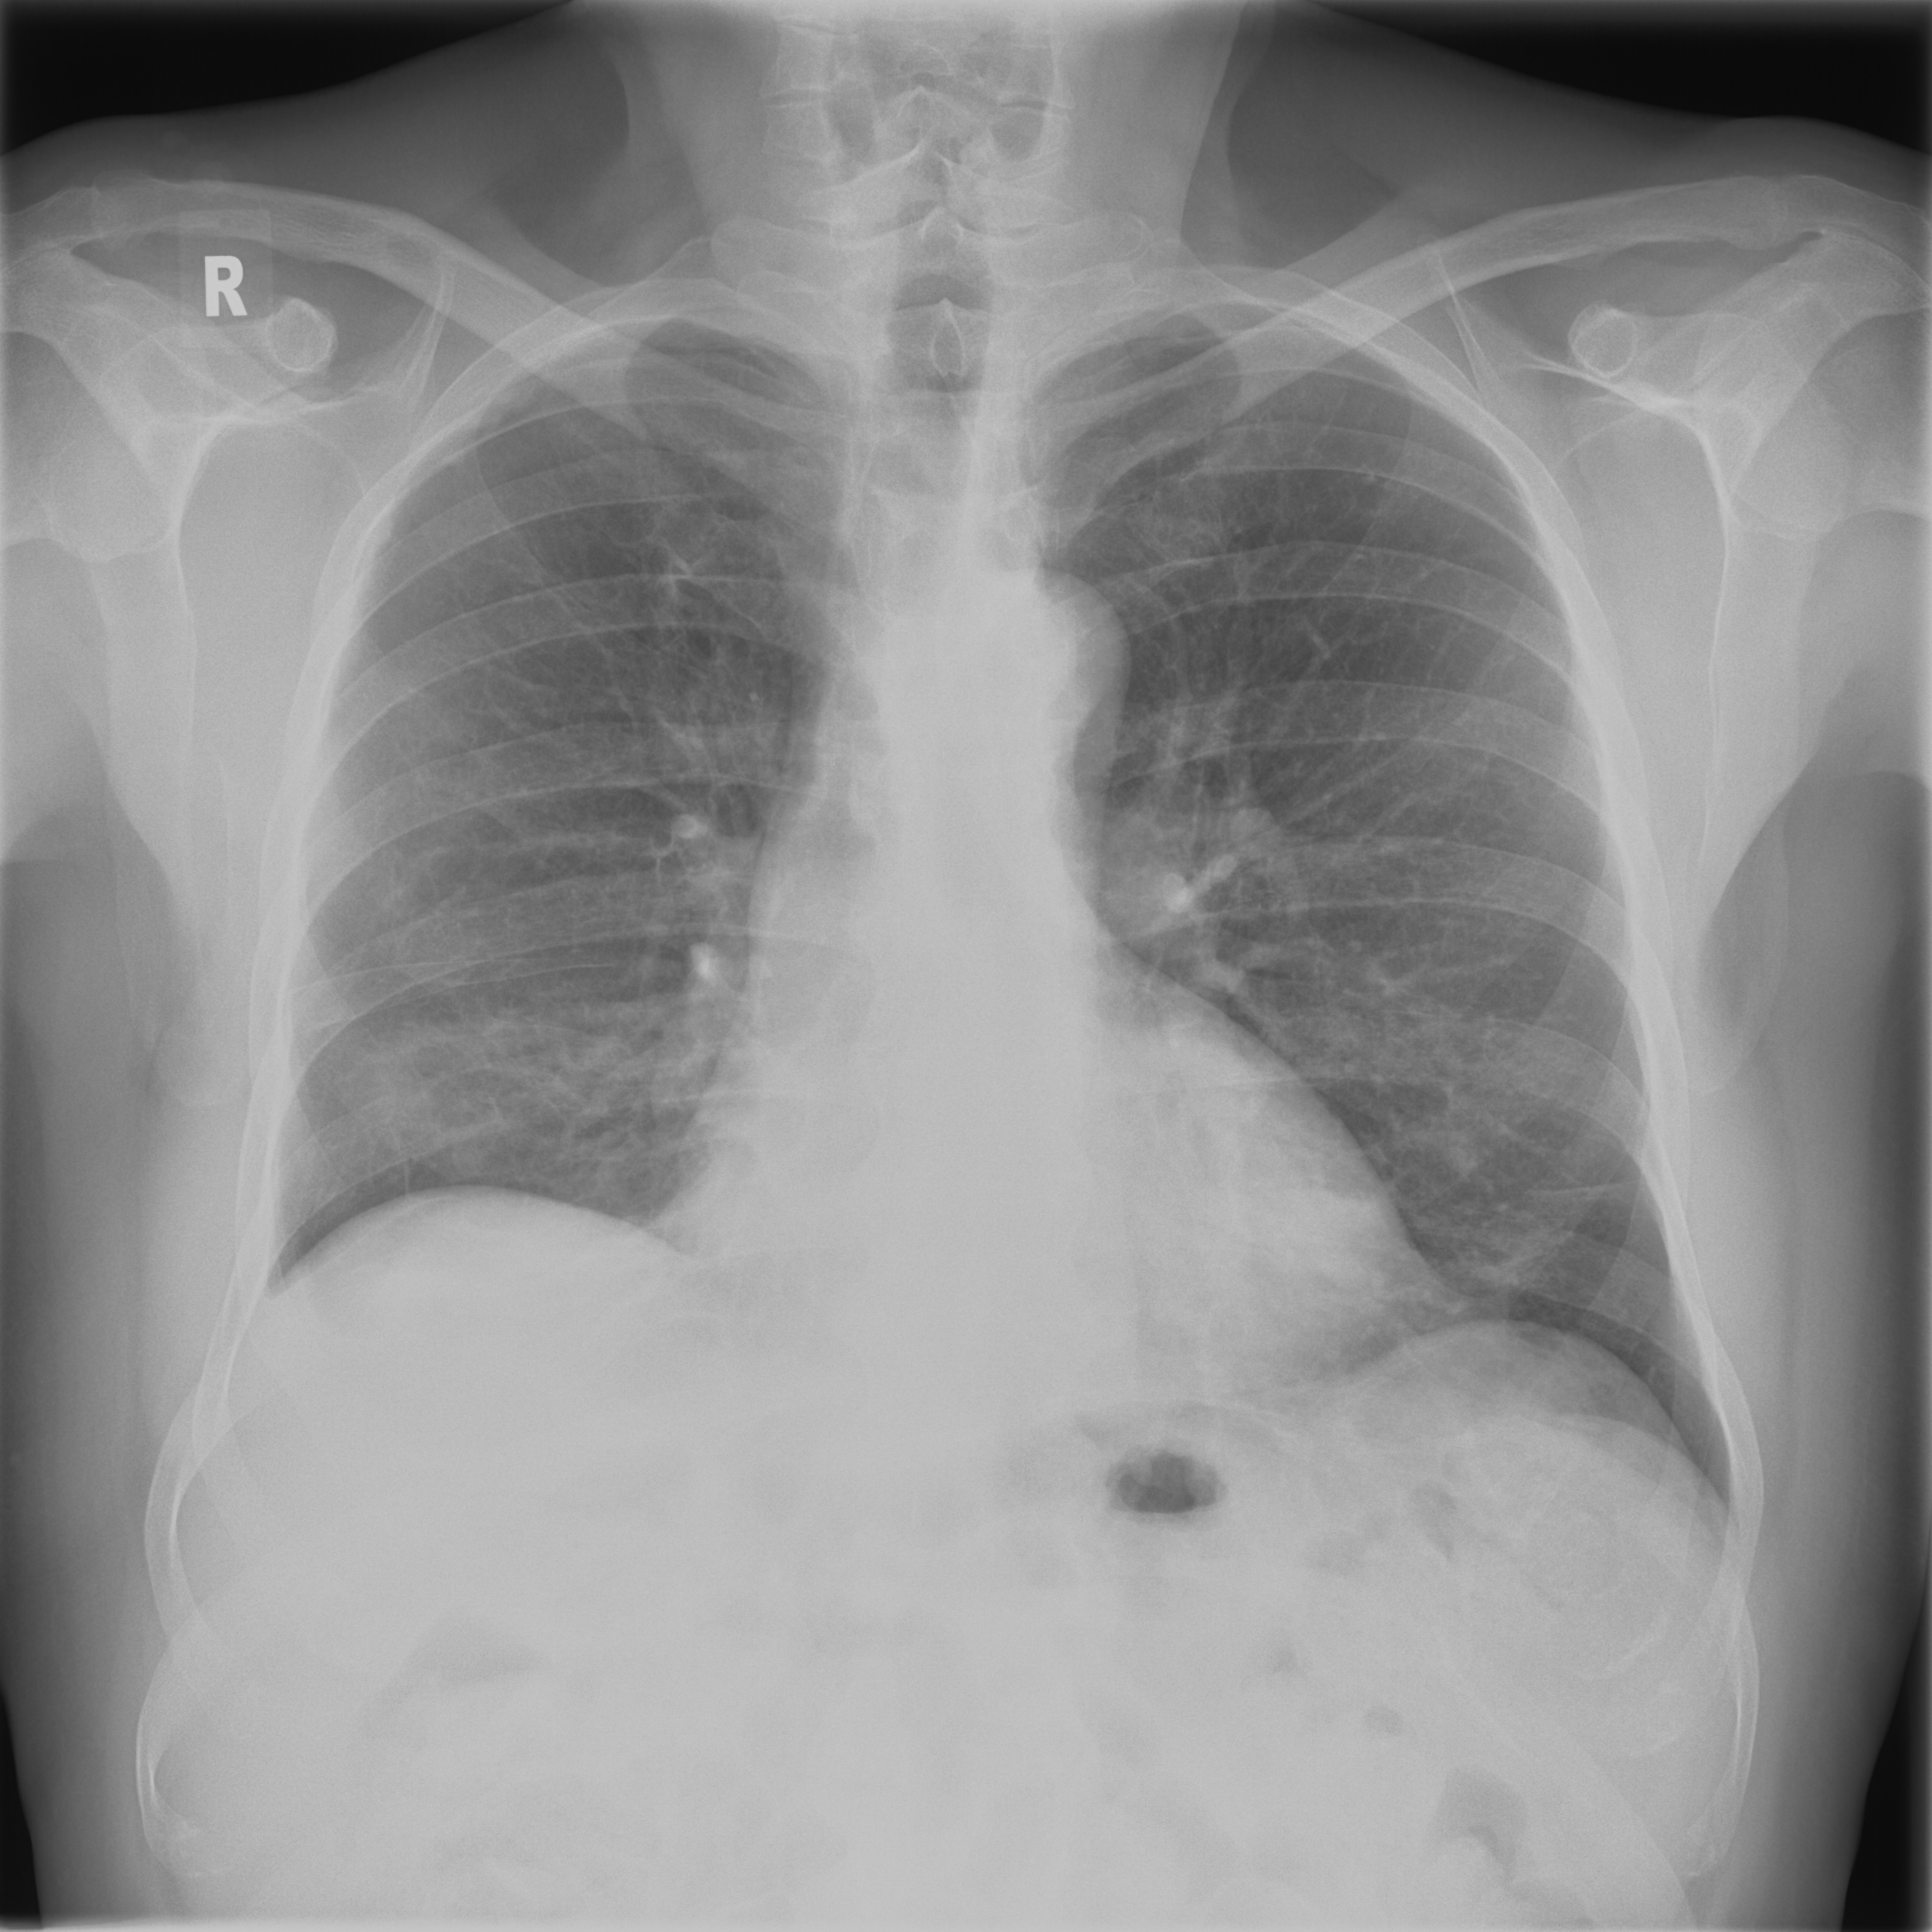

3.3.2 Data

Posteroanterior chest radiographs were acquired on two imaging systems (both Discovery XR656 HD models, GE Healthcare, USA) at Cambridge University Hospitals NHS Trust. Each scanner was being set up in the hospital with different post-processing parameters (chosen by the operating radiologists), which are used here as reference images, see Figure 7 and 8(a). Additional images, serving as real-life examples of lower quality, were produced for each radiographic exposure using multiple different post-processing settings. The post-processing was applied in the hospital directly on the scanner itself by adjusting parameters in the provided framework.

Refer to caption

(a) Reference

(b) (21.1, 0.90, 0.11)

(c) (19.5, 0.88, 0.16)

Figure 7: Chest X-Ray scans with different kinds of post-processing; (a) serves as reference and (b) is wrongly judged as better visualization by PSNR/SSIM/LPIPS.

FR-IQA mismatches

In Figure 7, contrast deviation and edge enhancement were reduced in (b), but increased in (c), the noise reduction algorithm was removed in both. The brightness was increased in both images but more so in (c) and low-contrast enhancement was removed in (b). The result is that (b) has relatively low contrast in the lungs compared to the reference (a) and radiograph (c). In Figure 8, edge enhancement has been dramatically increased in (b), whilst the contrast deviation and tissue contrast have been reduced. In (c), the brightness, tissue contrast and edge enhancement have been slightly increased. Consequently, (b) provides low contrast in the lungs with excessively prominent lung markings and vasculature which make it harder to detect abnormalities such as a pneumonia.

All of the chosen FR-IQA metrics wrongly judge (b) as the better image in the first example Figure 7, and the results in (b) and (c) of the second example Figure 8 are quite close, where PSNR and SSIM are also providing the wrong order. The tested measures are not suitable to evaluate the quality of data sets with X-Ray images that have large variations regarding contrast, luminance and sharpness.